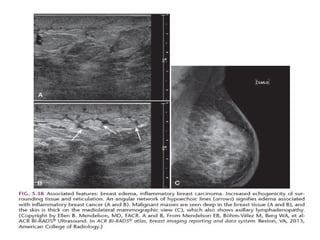

BI-RADS 4A in a 55-year-old woman who presented with a

palpable mass and swelling in her left breast

BI-RADS 4A ina 55-year-old woman who presented with a palpable mass and swelling in her left breast